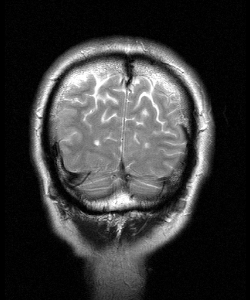

Dr Callaway has worked extensively in the field of

Alzheimer's disease,

specifically in understanding

and controlling

amyloid

formation.